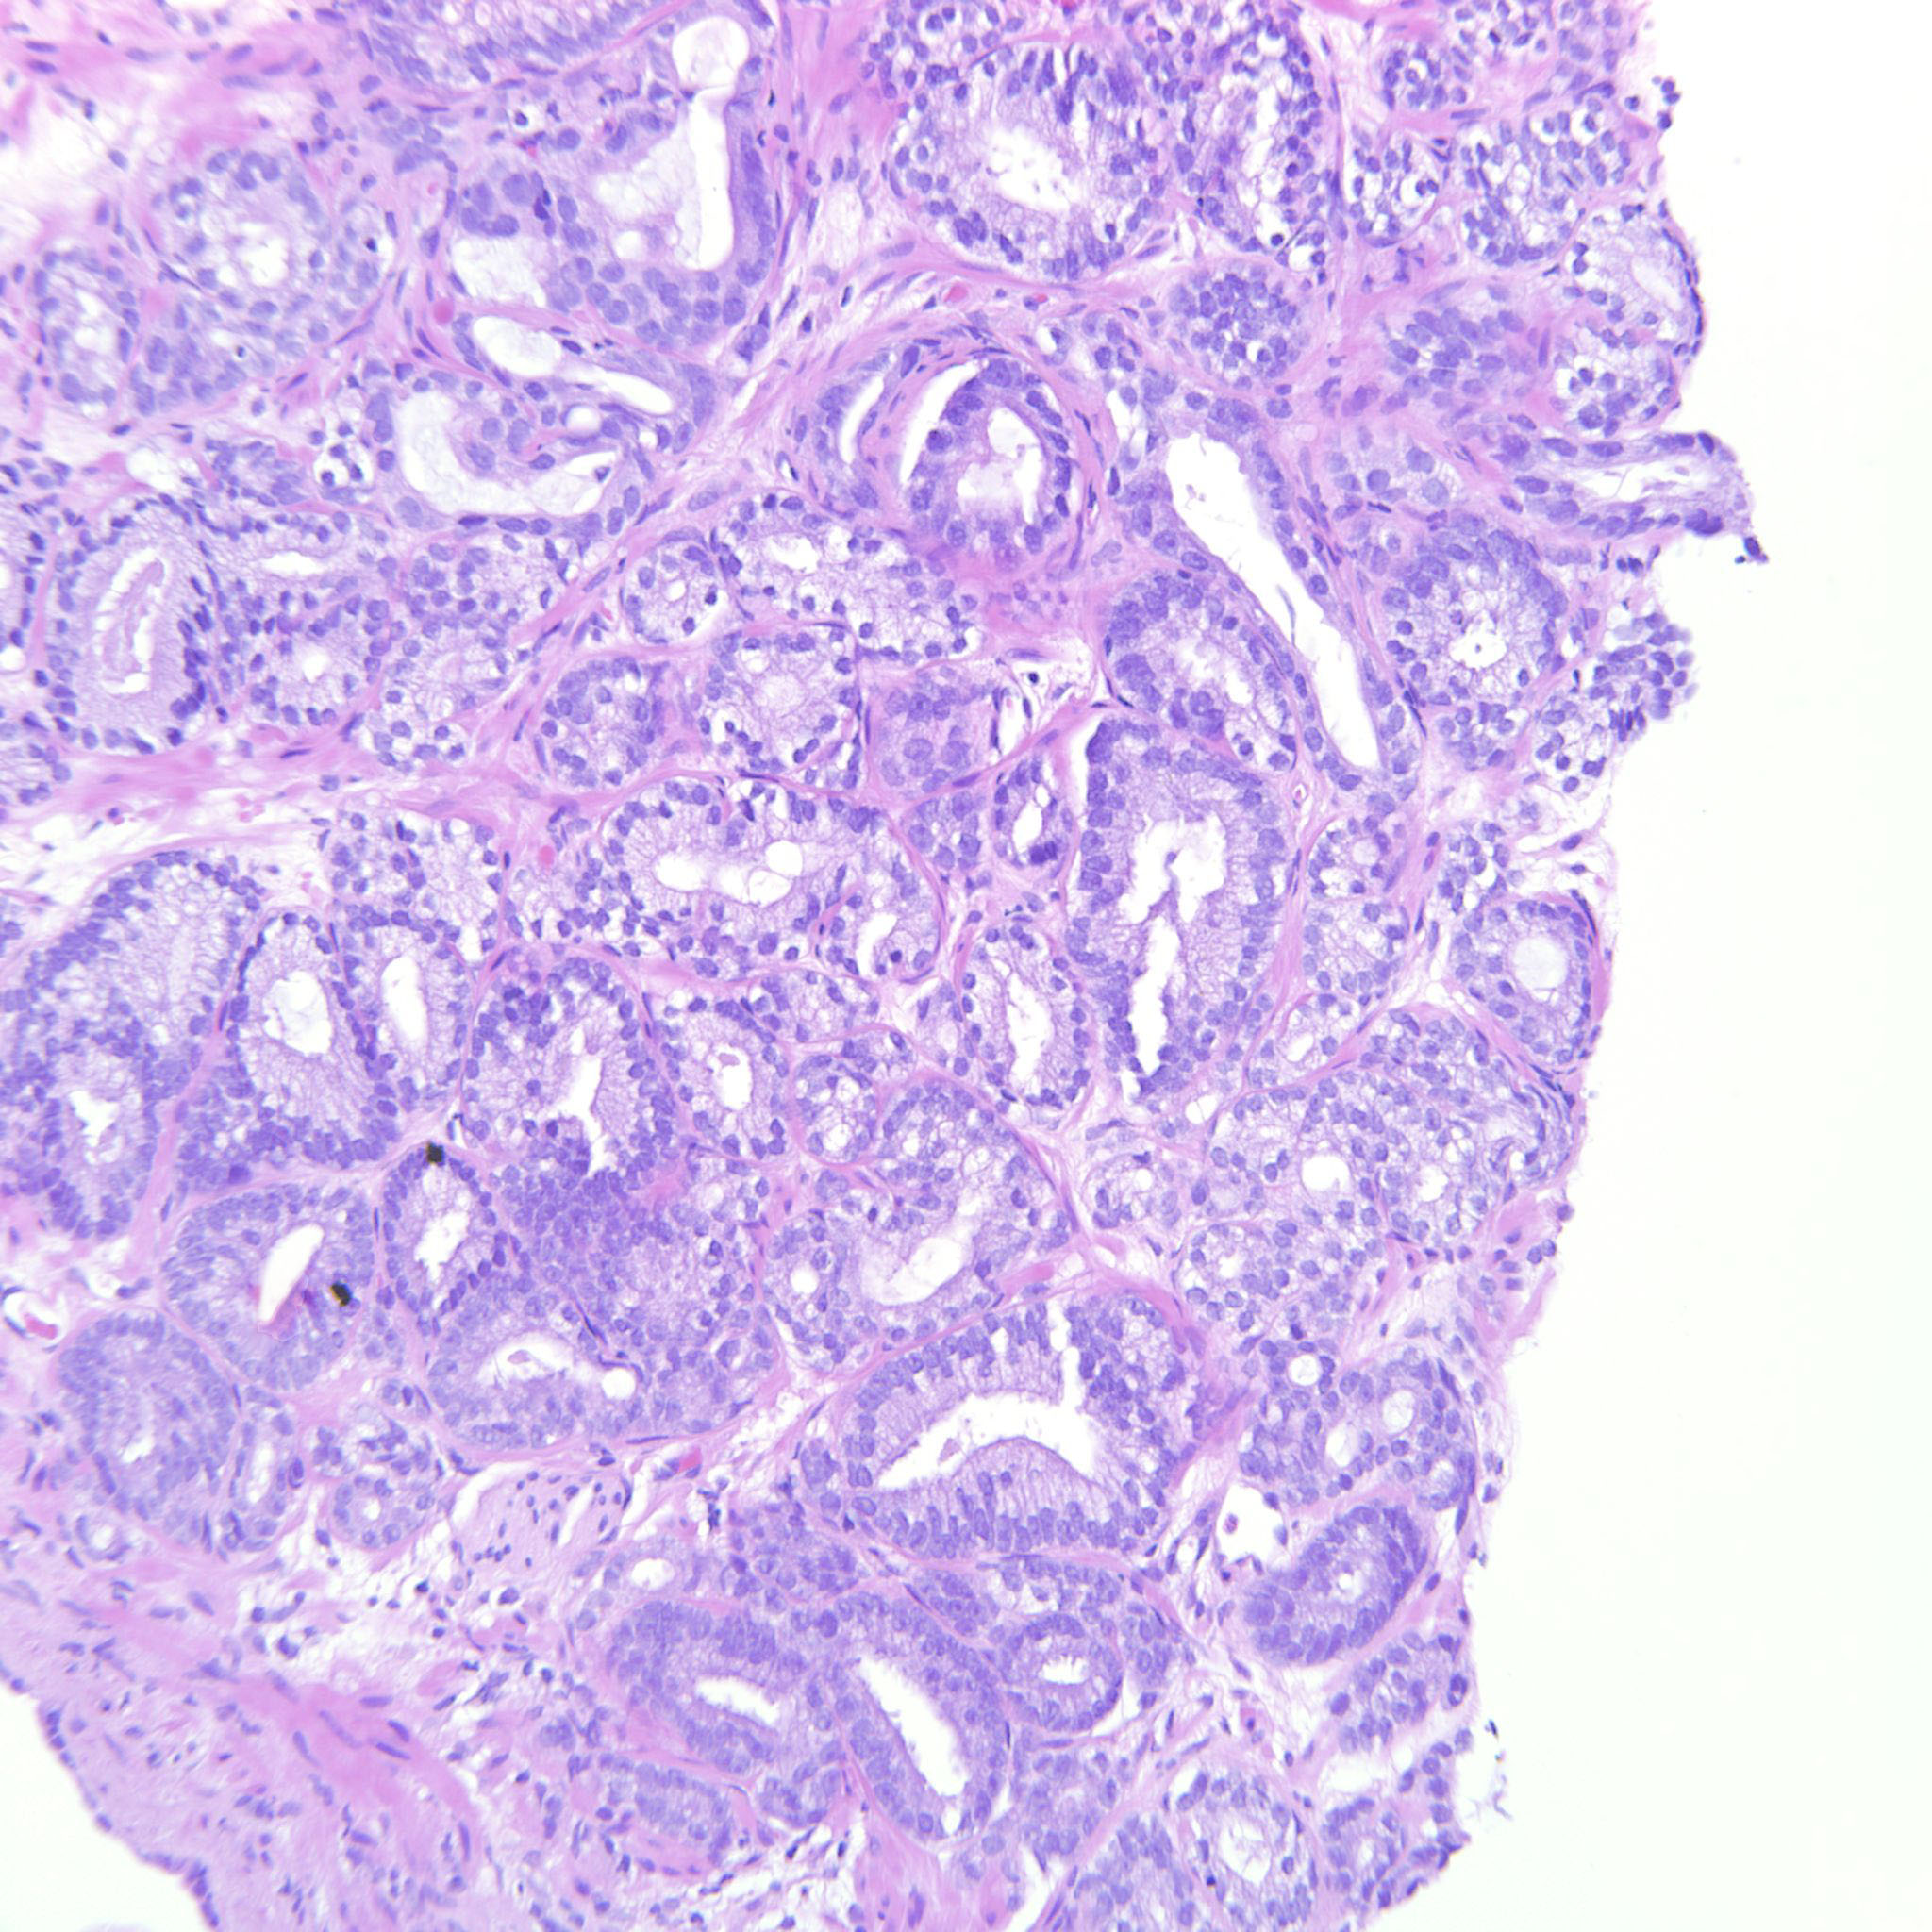

Consensus grade: GS 3+3=6 (ISUP 1)

3+3=6 with occasional seemingly poorly formed glands. These are however seen between well-formed glands and probably represent tangential cuts.

| Pathologist 19 | GS 3+3=6 (ISUP 1) | Borderline higher |

one gland looks like its trying to fuse |

| Pathologist 11 | GS 3+4=7 (ISUP 2) | Borderline lower | |

| Pathologist 12 | GS 3+4=7 (ISUP 2) | Typical | |